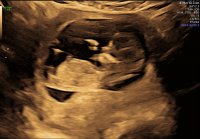

Alt bra på UL. Alle organer ser bra ut. Er 14+4 målt til 14+6. Legen var rimelig sikker på at vi venter en liten jente:talk017